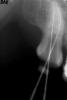

zybnaya feya Опубликовано 31 января, 2011 Поделиться Опубликовано 31 января, 2011 (изменено) Сегодня пришла такая пульпитная красотка. http://s41.radikal.ru/i092/1101/a9/f870fab317c3.jpg Я пока рабочую длину померяла,влезла протейпером,ломанула его мигом)) Удалось обойти обломок,достать не получилось. Думаю что в МБ была дельта крупная или МБ2 отходил,тейпер в нее и врезался Устья нашла только три. МБ щелевидное. http://s52.radikal.ru/i138/1101/c5/1ecde9d5ef1d.jpghttp://s47.radikal.ru/i117/1101/97/a14cdbda90c5.jpg получилось так обтурировать(АН+,термафил) http://s41.radikal.ru/i094/1101/3e/bf6508bd65d6.jpg Изменено 31 января, 2011 пользователем zybnaya feya Ссылка на комментарий

Kivilgar Опубликовано 31 января, 2011 Поделиться Опубликовано 31 января, 2011 Я пока рабочую длину померяла,влезла протейпером,ломанула его мигом)) Удалось обойти обломок,достать не получилось. Думаю что в МБ была дельта крупная или МБ2 отходил,тейпер в нее и врезался Аня, а по калибровочному такое ощущение (наверно ложное) что он (отломок) не плотно На контрольном если не знать то и не видно. А может стоило 2 пройденных обтурировать, а с отломком на несколько дней с гидроокисью отправить, замечала же наверно,что бывает откисает ? Ссылка на комментарий